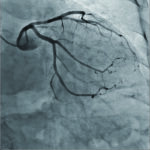

Nova obitelj interventnih sustava Alphenix donosi slike veće jasnoće i preciznosti. U kombinaciji s vodećim tehnologijama za optimizaciju doze, poboljšanim tijekom rada i brojnim novim alatima, Alphenix nastavlja predanost tvrtke Canon Medical u pružanju potpore vama i vašoj misiji kako bi pacijentima omogučili sigurno, točno i brzo slikanje.